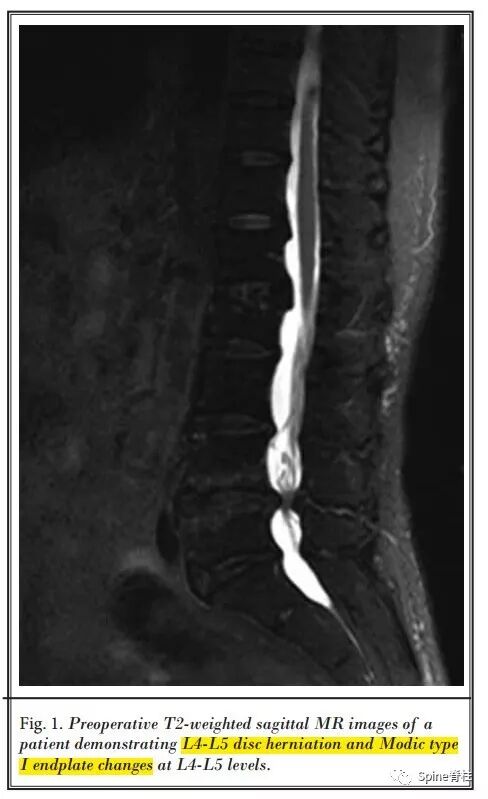

3. 来自中国的回顾性研究(2017. Pain Physician)

上海交通大学附属第六医院放射科Tian等将PCD与经皮腰椎间盘切除术(percutaneous lumbar discectomy,PLD)相结合治疗7例症状性腰椎间盘突出症伴终板 I型 Modic改变患者,采用局麻下后外侧入路,先进行椎间盘切除,然后进行PMMA骨水泥灌注,随访1年,VAS和ODI评分显著改善。仅1例出现骨水泥穿刺通道渗漏伴轻微腰痛,24h后缓解,未见其他明显并发症。

图: 左图为PLD(先),右图为PCD(后)

最后作者总结,PLD+PCP可作为老年腰椎间盘突出症伴I型Modic终板改变患者的可选治疗方法,对于因一般情况不佳难以耐受传统开放手术或不愿意接受开放手术的患者来说,这似乎是一个选择。此外,这是一种微创技术,可在清醒镇静下进行,并发症发生率极低,住院时间短。